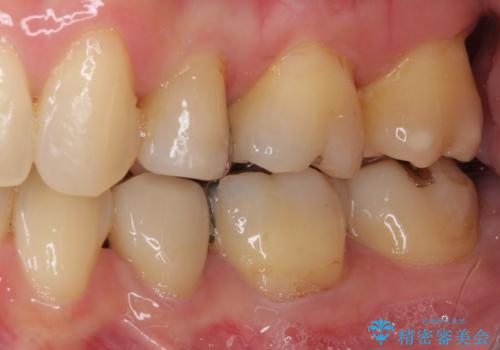

- 上下前歯の叢生を気にして来院された患者様です。

費用を抑え、期間もあまりかけずに治療をしたいとのことで、インビザライン・ライトを用いて矯正治療を行うこととしました。

矯正治療後には、下顎臼歯の目立つ銀歯をセラミックインレーにて修復治療を行いました。

軽微な後戻りの治療であったため、十分に治療を行うことができました。

口を開けたときに金属が見えなくなり、患者様には大変満足していただきました。